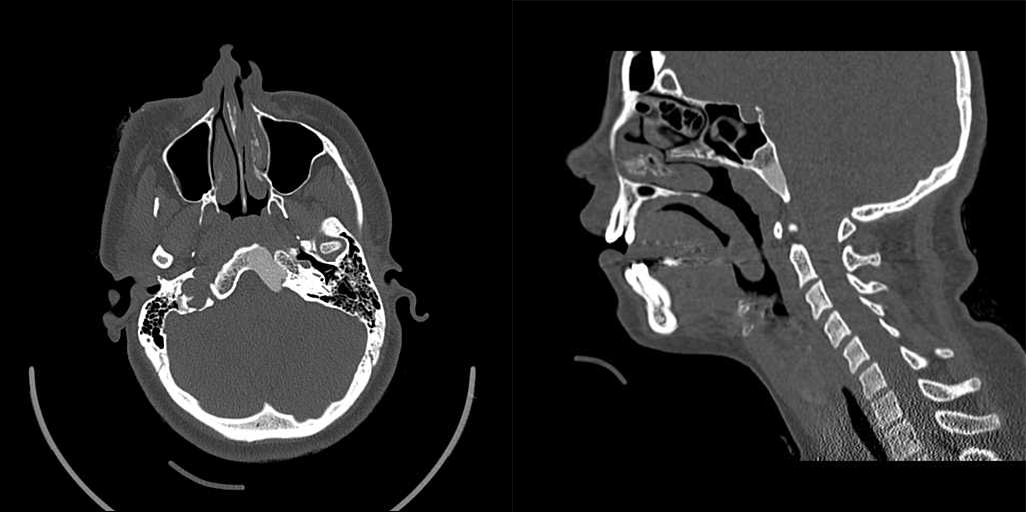

(注:枕骨斜坡偏左份骨质呈膨胀性、磨玻璃样密度增高影改变,边界较清,临近骨皮质变薄,未见明显骨膜反应。)

注:颅底骨(颞骨鳞部、右侧蝶骨体、蝶骨大翼、右侧筛窦壁)膨大,呈磨玻璃样改变,右侧翼管、圆孔变窄。T1WI 呈低信号,T2WI 呈低信号,增强 T1WI 呈轻度不均匀强化。